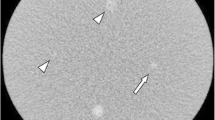

Quantitative analysis

Quantitative measurements were performed at a commercially available workstation (Advantage Windows 4.2; GE Healthcare) by experienced radiology research personnel who was blinded to the image review results. The seven image sets were displayed side by side with a preset soft-tissue window (window width, 350 HU; window level, 40 HU). We measured the image noise and attenuation values of the liver, portal vein, and paraspinal muscle, as also described in previous reports [14, 15]. Objective image noise was measured for 525 image sets (seven image sets each from 75 patients) as the standard deviation of the pixel values from a circular or ovoid ROI (10–50 mm2) placed in a homogenous region of subcutaneous fat of the anterior abdominal wall. To ensure consistency, all measurements were performed three times at the level of the main portal vein, after which the mean values were calculated.

Mean CT attenuation values (in Hounsfield units) of the portal vein, liver parenchyma, and paraspinal muscle were obtained on the portal phase of CT scanning. The attenuation of the portal vein was measured from a single ROI (10–50 mm2) placed at the portal vein confluence level. The liver attenuation was recorded as the mean of the measurements of four ROIs (50–100 mm2) in the medial and lateral segments of the left hepatic lobe and in the anterior and posterior segments of the right hepatic lobe [14]. Areas of focal changes in the liver parenchyma, visible blood vessels, bile ducts, and prominent artefacts were carefully avoided in the ROI measurements. The attenuation of the paraspinal muscles was recorded as the mean attenuation of two ROIs (10–50 mm2), while taking care to avoid macroscopic fat infiltration in the right and left paraspinal muscle at the level of the right portal vein. For all measurements, the size, shape, and position of the ROIs were kept constant by applying the copy-and-paste function at the workstation.